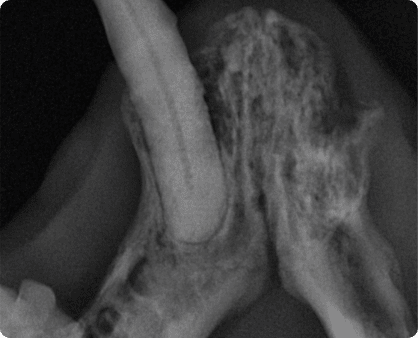

외상, 중증 치주염에 의해 턱 뼈가 골절되는 상태.

특히 하악 전치부 결합부의 분리가 흔하게 관찰된다.